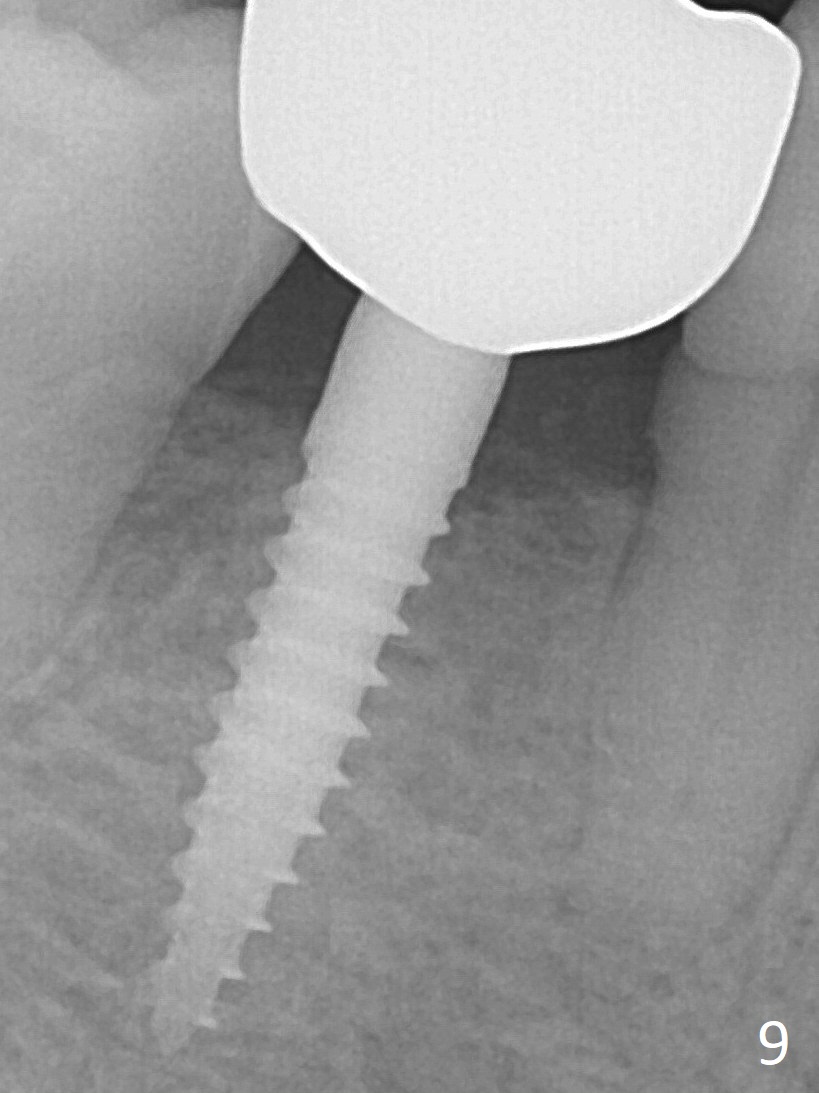

A 3x12(2) mm 1-piece implant is placed (Fig.4) with insertion torque > 40 Ncm. There is no bone loss 3 months postop (Fig.6), 3.5 months post cementation (Fig.9) or 3 years 7 months post cementation (Fig.12).